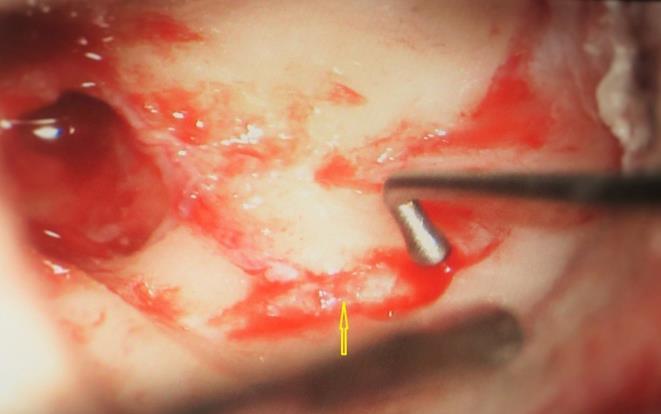

A 13 year old girl presented in ENT outpatient department with complains of recurrent right ear purulent discharge from pre and post auricular area for last 5 years. She had a history of incision and drainage in right post auricular area six months prior for similar complain. On local examination, there was right Grade II8microtia with atretic External Auditory Canal (EAC) and pre-auricular skin tag (Figure 1). A small fistulous opening was also seen in right cavum conchae region. Left ear examination was normal with intact tympanic membrane. Tuning fork tests using 256 and 512 Hz tuning forks showed moderate to severe conductive hearing loss in right ear with Rinne’s test positive in left ear. HRCT scan of temporal bones showed membranous atresia of right EAC with grade II microtia. Soft tissue density was seen filling the EAC and the entire middle ear cavity (Figure 2A). A CT based fistulogram done four months before our consultation identified multiple fistulous tracts situated in post auricular region and anterior to stylomastoid foramen in inframastoid region. These fistulous tracts were communicating through middle ear cavity (Figure 2B). There was associated erosion of posteroinferior and anteroinferior wall of EAC. Ossicles were dysplastic or eroded. Inner ear structures were normal. Patient underwent right radical mastoidectomy with wide conchal meatoplasty under general anaesthesia. Intraoperatively, there was right EAC membranous atresia with fistulous opening in cavum conchae. Cholesteatoma sac was seen filling the mastoid antrum area extending into middle ear cavity and EAC with erosion of posterior canal wall. Except remnant of malleus head which was fixed to epitympanic wall, no other ossicle was found. Oval window area showed bony depression without any overlying stapes footplate (Figure 3). Lateral semicircular canal bulge, facial nerve canal and chorda tympani were found at their usual locations (Figure 4). Obliteration of mastoid cavity posterior to vertical segment of bony facial canal was done using pedicled temporalis muscle flap to reduce the size of postoperative cavity. Middle ear cavity was covered with temporalis fascia graft.

Figure 3.Arrow pointing towards oval window area